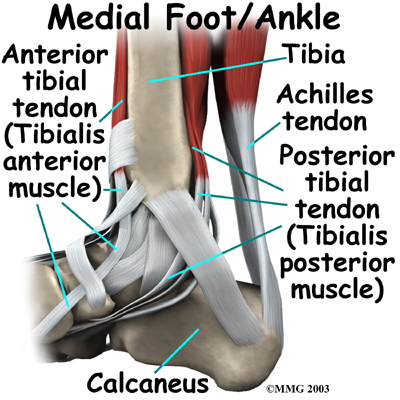

The ankle joint is also supported by nearby tendons. The large is the most important tendon for walking, running, and jumping. It attaches the calf muscles to the calcaneus (heelbone) and allows us to raise up on our toes. The attatches one of the smaller muscles of the calf to the underside of the foot. This tendon helps support the arch and allows us to turn the foot inward.

The anterior tibial tendon allows us to raise the foot. Two tendons run behind the outer bump of the ankle (the lateral malleolus). These two tendons, called the peroneals, help turn the foot down and out.

- The posterior tibialis muscle supports the arch and helps turn the foot inward.

- The anterior tibialis pulls the ankle upward.